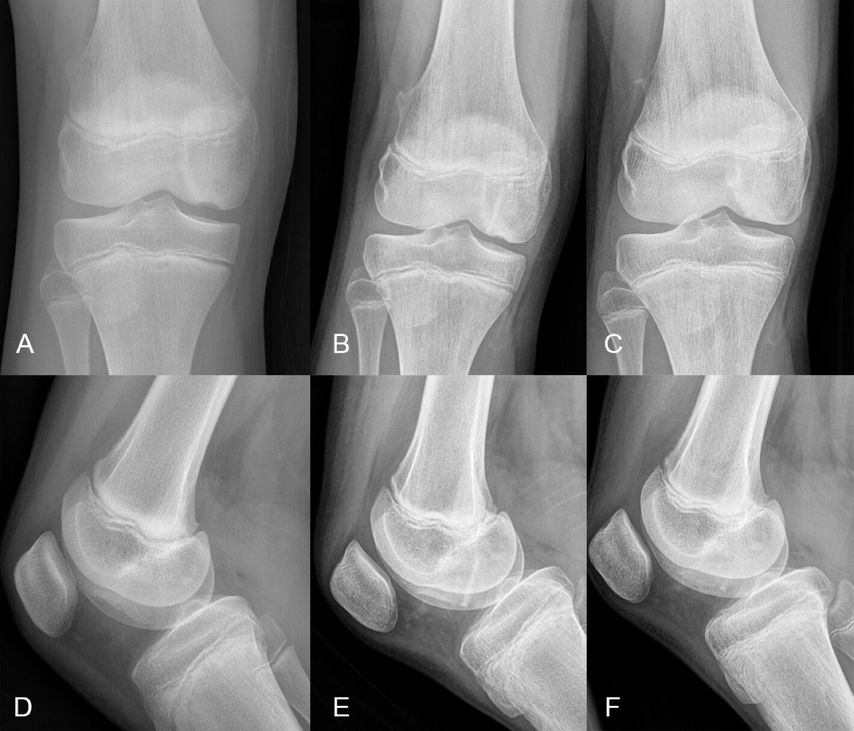

Eine exakte und umfassende radiologische Abklärung ist Voraussetzung für eine fundierte Therapieentscheidung. Dies beinhaltet jedenfalls eine nativradiologische Bildgebung in 2 Ebenen. Abhängig vom betroffenen Gelenk sind hier gegebenenfalls zusätzliche Untersuchungen zu fordern. Bei OD-Läsionen des Kniegelenkes sollte zusätzlich eine Rosenberg-Aufnahme oder eine Tunnelaufnahme angefertigt werden, in der sich OD-Läsionen an der Prädilektionsstelle am posterolateralen medialen Femurkondyl überlagerungsfreier projizieren (Abb.1). Weiters sollte eine radiologische Abklärung der Gegenseite erfolgen, da in bis zu 29% der Fälle beide Kniegelenke betroffen sind, wovon wiederum bis zu 40% der Fälle asymptomatisch sein können.10 Die ergänzende Anfertigung von Ganzbeinröntgenaufnahmen im Stehen zur Vermessung der Beinachse ist essenziell. Bei entsprechender behandlungswürdiger Achsdeviation sowie noch geöffneten Wachstumsfugen sollten zusätzlich a/p-Röntgenaufnahmen der linken Hand zur Erstellung einer Wachstumsprognose erfolgen. In Abhängigkeit vom zu erwartenden Korrekturpotenzial kann zusätzlich zur operativen Therapie des Knorpelschadens auch ein Eingriff zur Wachstumslenkung indiziert sein.

Abb. 1: 12-jähriger männlicher Patient mit einer Osteochondritis dissecans am medialen Femurkondyl a/p (A), seitlich (B), Tunnelaufnahme (C)